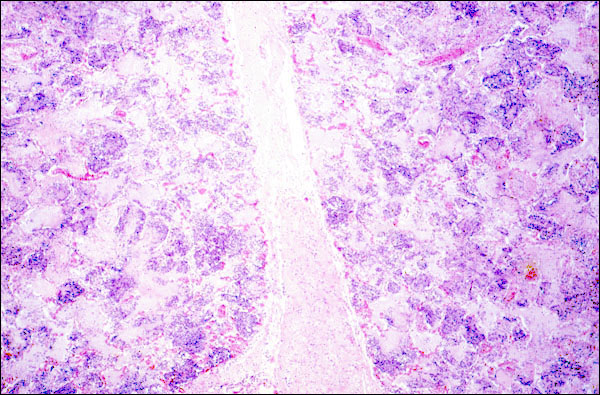

Your text tells you that an exudate differs from a transudate, in that the former contains more protein (specific gravity >1.015) and often contains leukocytes. This photomicrograph of an acutely inflamed lung dipicts clearly what an exudate is. Note that the alveoli, as well as the interstitial tissue that separates the two lobules, are filled by pink material. That is the way that protein looks in a routine slide stained with hematoxylin and eosin dyes (H & E, the routine stain used to study tissues microscopically). The protein was contained in edema fluid, which must have been plentiful, because the alveoli are distended, and the two lobules are uncharacteristically separated from each other, i.e., the interstitial space is widened. In this field, you can additionally see that leukocytes are present in this exudate, although they cannot be specifically identified as to type at this low power. They form the basophilic aggregates that are scattered widely in the alveolar spaces. Another clue that this is acute pneumonia is the hyperemia that is seen throughout this section.